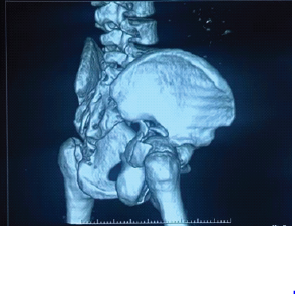

Aneurysmal Bone Cyst Presenting as a Pathological Subtrochanteric Femur Fracture in an Adolescent: A Case Report

Chandrashekhar R Rai , Sandeep V Gavhale , Vijaysing Chandele , Alok P Yadav , Chinmay S Torne , Vishal B Karpe